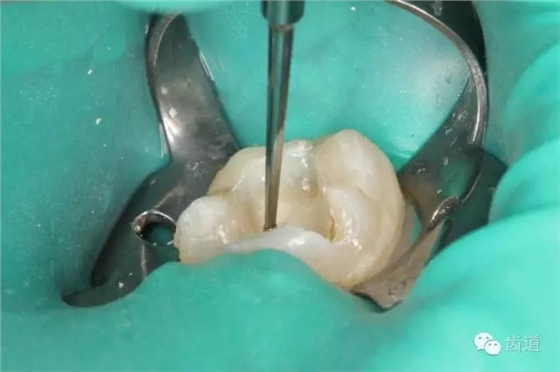

4. 初步開髓

5. Endo-Z揭全髓室頂

6. 可見髓腔內(nèi)壞死牙髓組織,無滲出

7. 3%次氯酸鈉浸泡髓腔5min

8. 浸泡后超聲清理髓腔,去除髓腔內(nèi)殘留牙髓組織